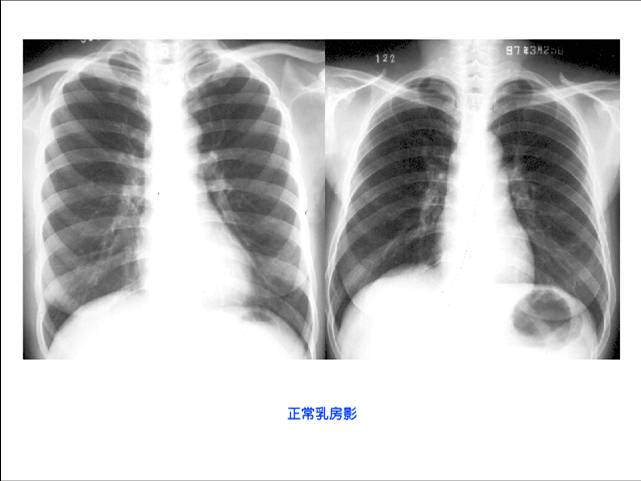

照片名称:正常乳房影